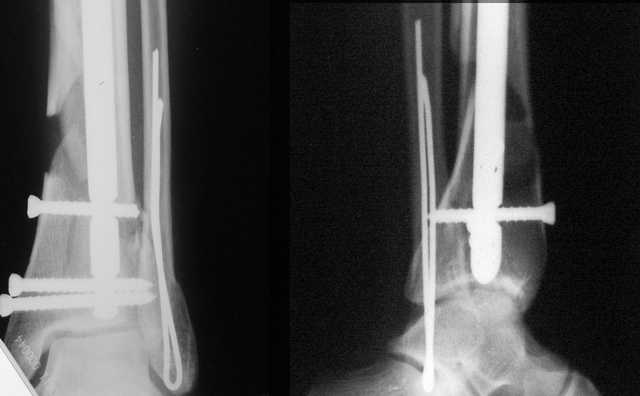

Да и нет! Зависит от перелома и способа остеосинтеза. А результат? (01)

А.Миронов

Кликните для загрузки файла 01.jpg

65KB (66785 bytes)

Мы же говорили о проксимальном плече. При переломе tibia, конечно, речи о двух Y-спицах нет. Еще раз о них - пружинящая подвижность без "срезающих" перемещений фрагментов - дополнительный стимул к образованию периостальной мозоли.

А в данном случае - у нас был бы применен locked nail с еще меньшими дырочками на коже и с возможностью полной нагрузки немедленно после операции. Какие тут аргументы в пользу выбора пластины, а не интрамедуллярного гвоздя?